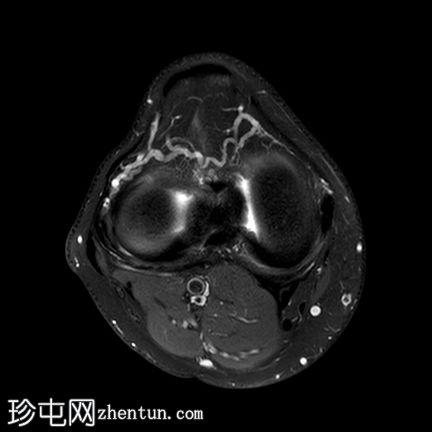

轴位PD脂肪抑制序列

内侧半月板(体部)内缘呈波浪状,符合半月板皱褶。

延伸至关节面的线状高信号,符合水平撕裂。

前交叉韧带(ACL)近端高信号提示部分撕裂。

股骨内侧髁后方关节积液及骨髓水肿。

半月板皱褶在矢状位图像上表现为膝关节半月板内缘呈波浪状。它与半月板撕裂的发生率增加无关,不应与半月板撕裂混淆,尽管在本病例中两者同时存在。